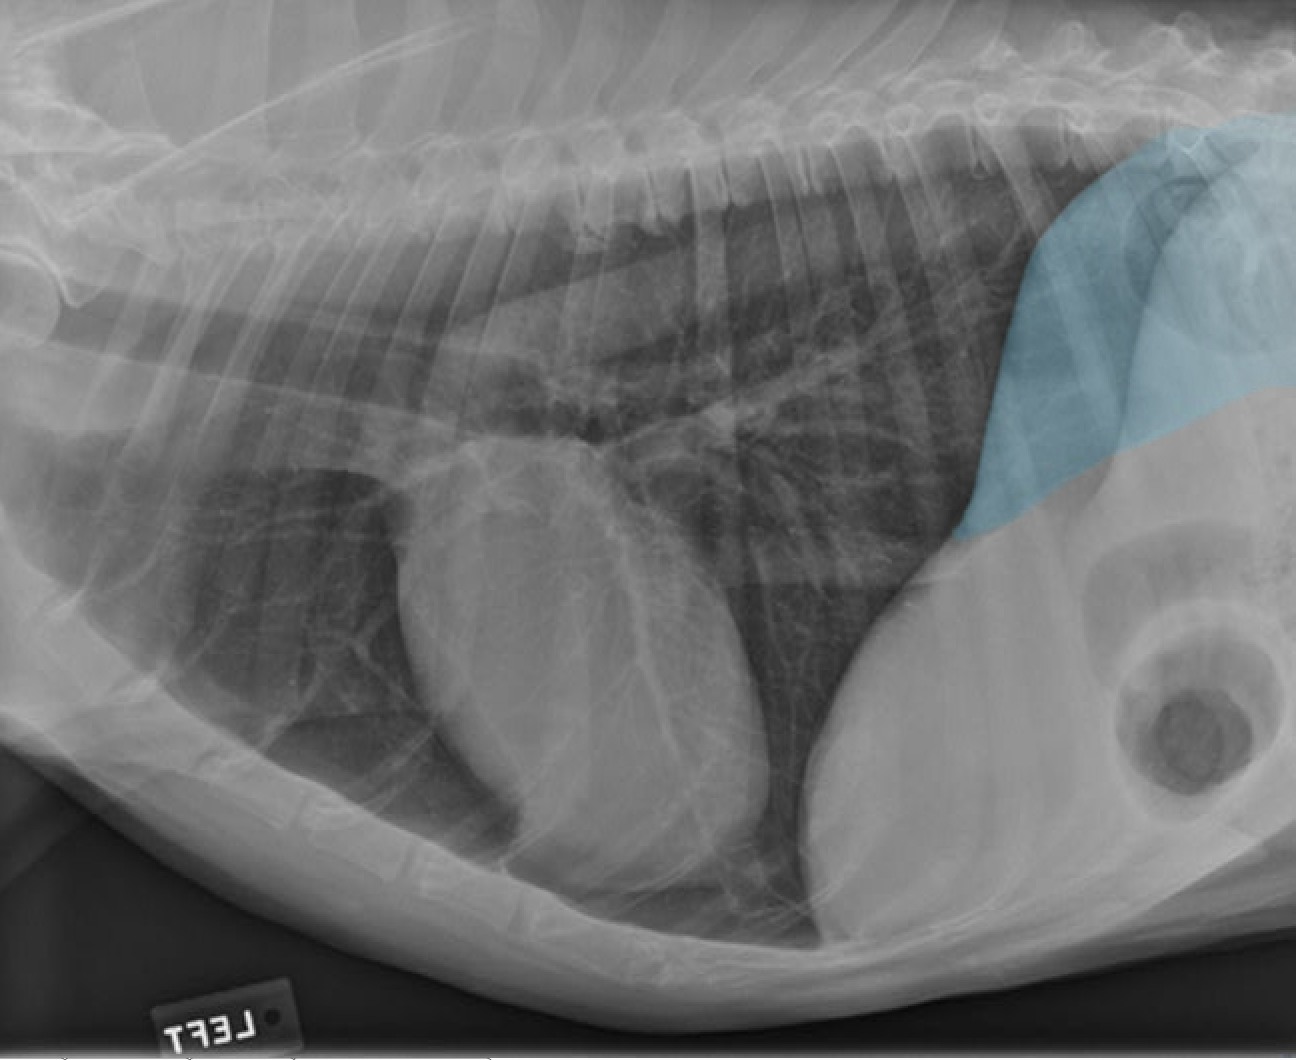

identify the structures

identify the pulomary arteries

identify the aorta

identify the ventral mediastiunum

identify the scapula

identify the ventral lung lobes